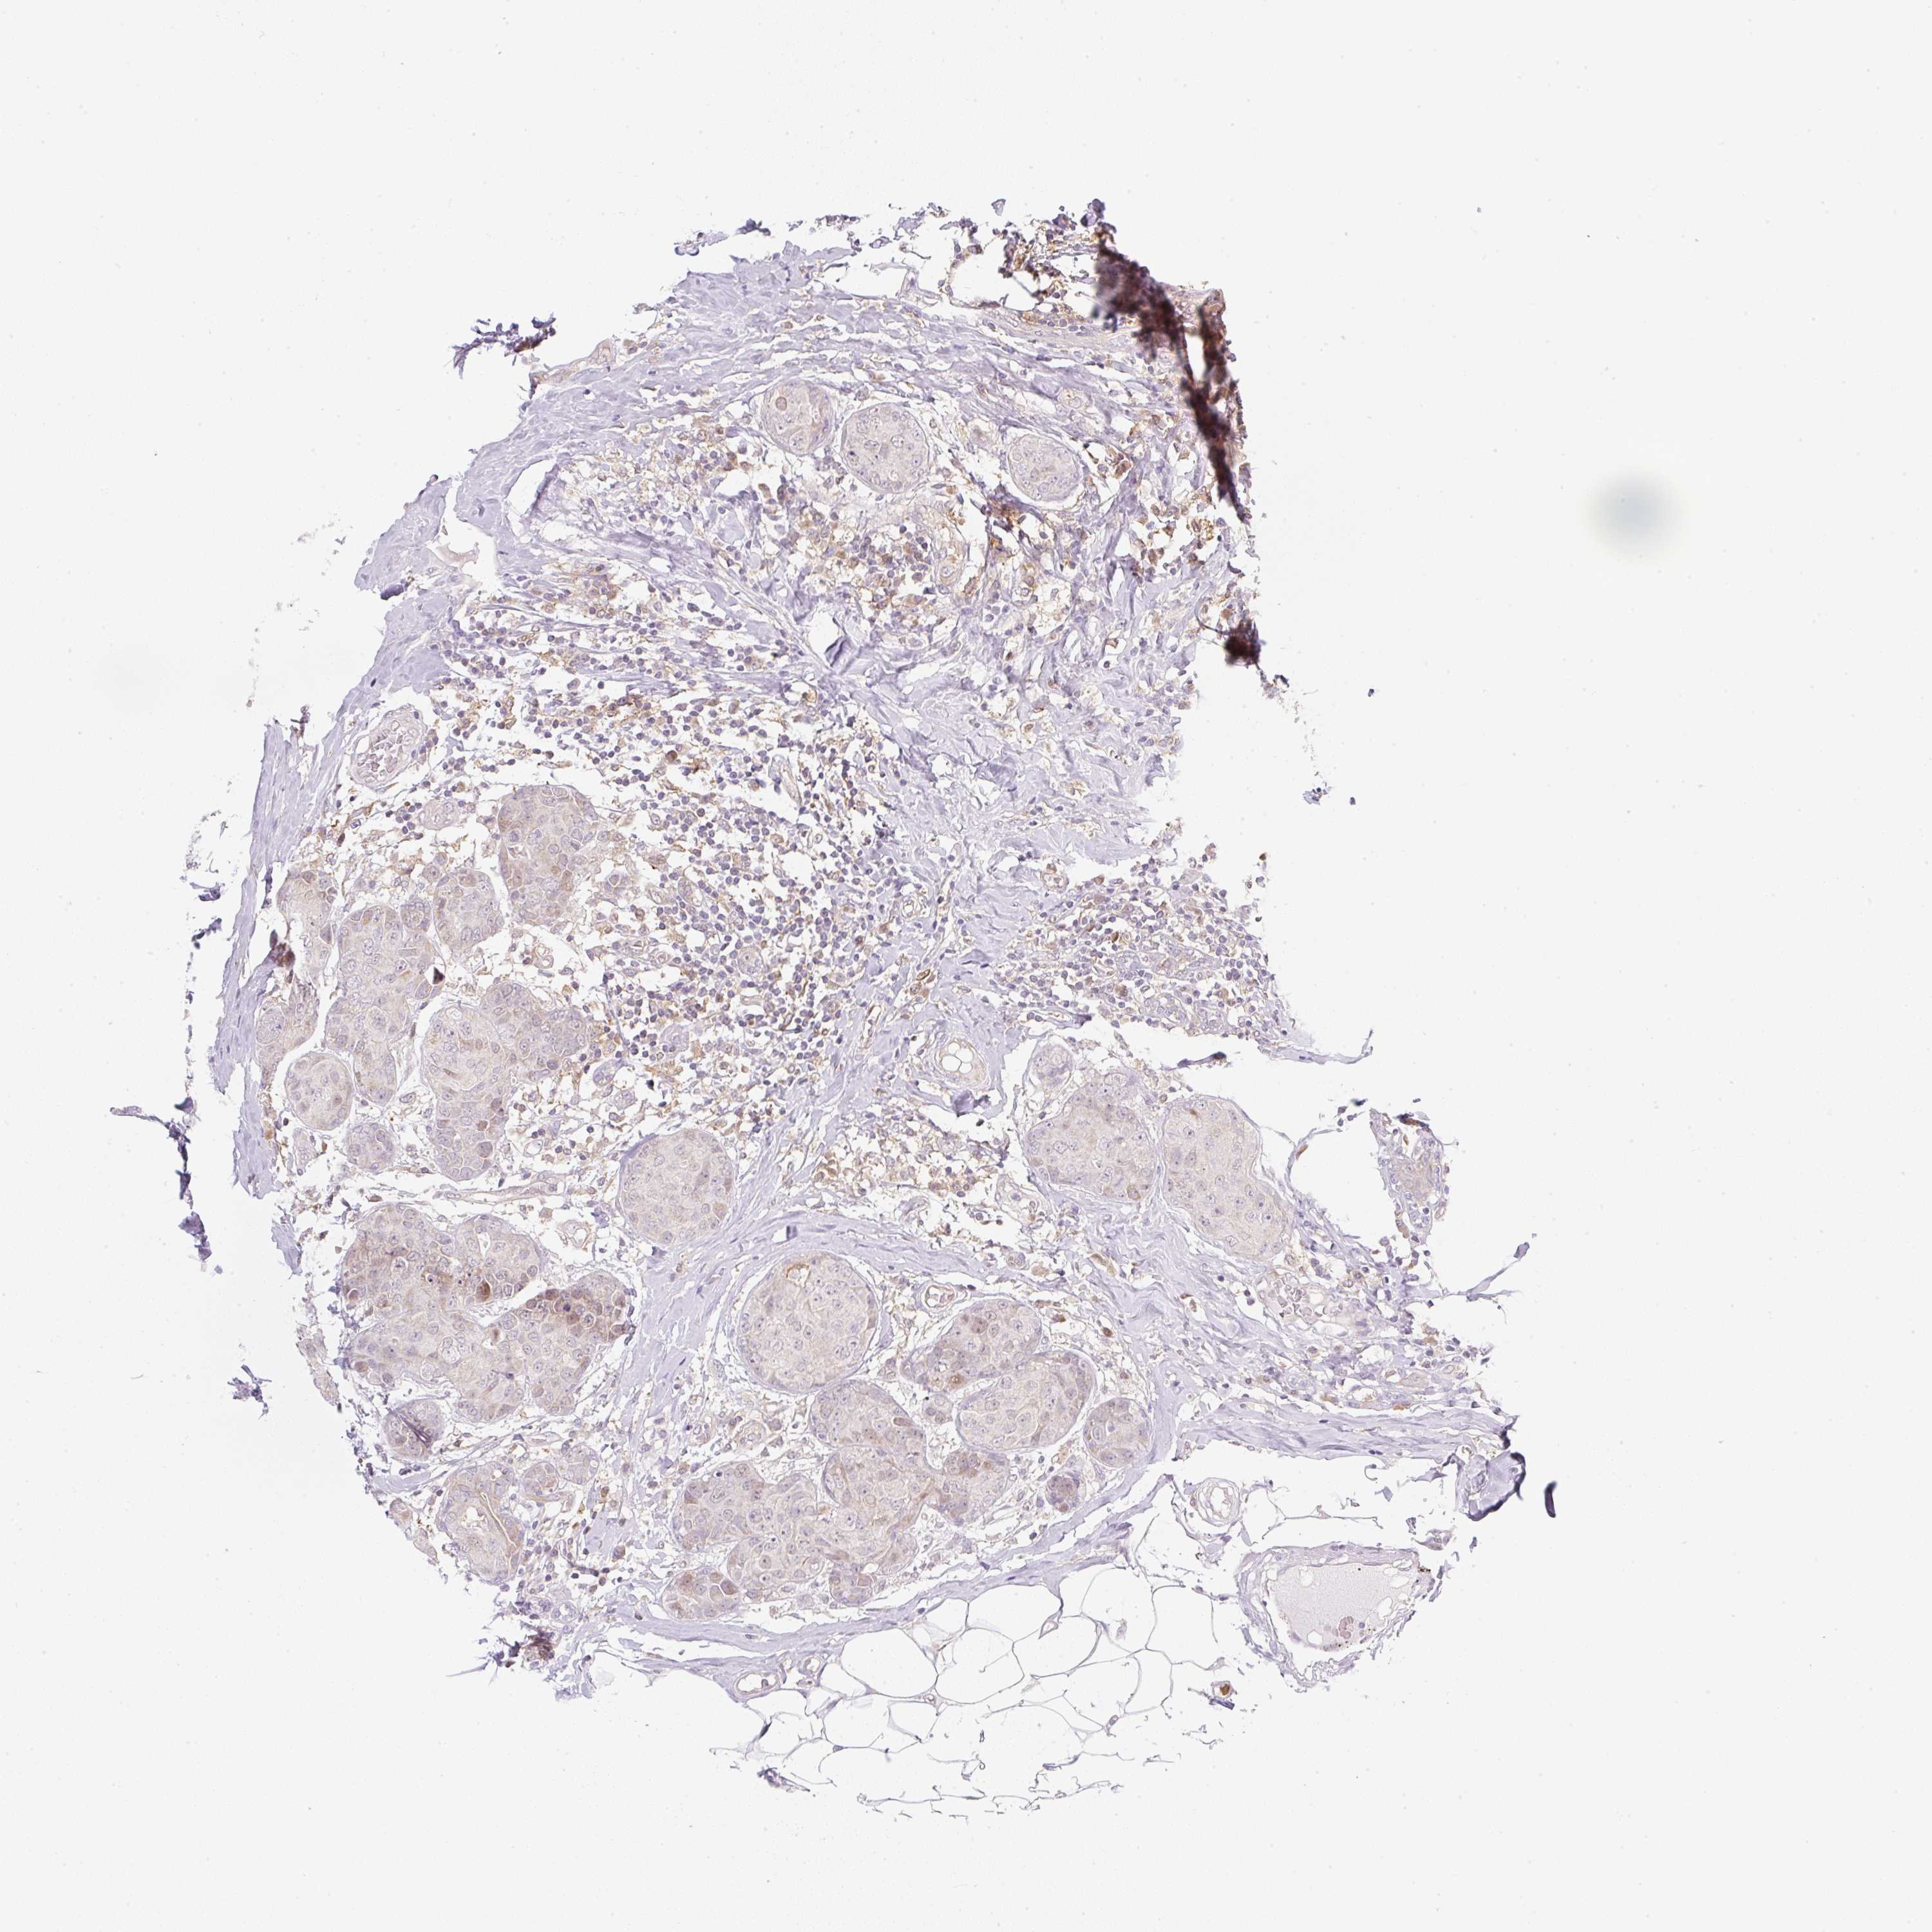

CANCER BREAST CANCER Show tissue menu

BRCA TCGA BRCA VALIDATION PROTEIN EXPRESSION